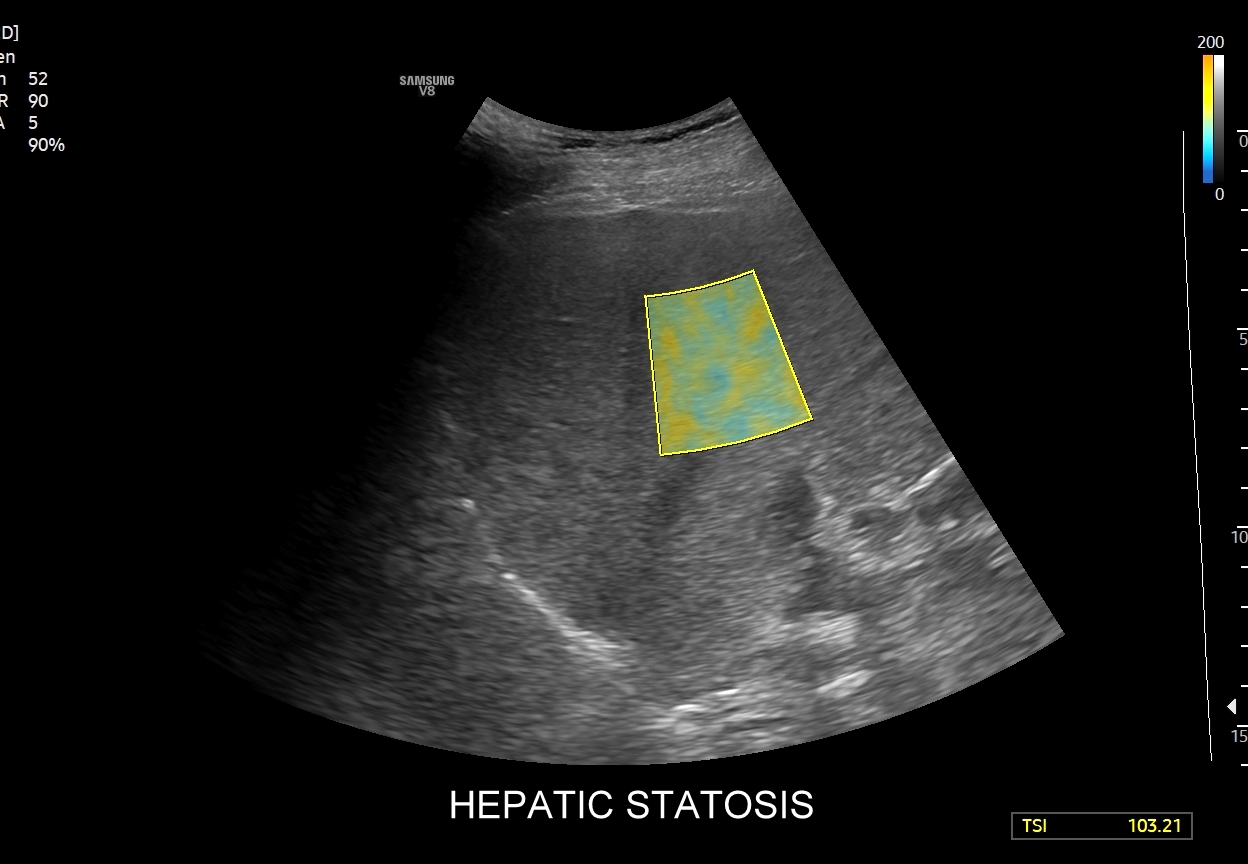

- Ilościowa ocena stłuszczenia wątroby QUS.

Multiparametryczne badanie USG (MPUS) jest rozwinięciem klasycznego USG jamy brzusznej zwykle w formie jednoczasowego zastosowania różnorodnych technologicznie trybów obrazowania USG, zarówno tzw. „nowych”, jak i „starych”. Wśród nowych najważniejszym jest obrazowanie mikrounaczynienia (MVI / MVF), a w dalszej kolejności tryby elastograficzne oraz metody ilościowej oceny stłuszczenia wątroby. Wymienione „nowe” modalności w połączeniu ze „starymi”, przede wszystkim z Dopplerem spektralnym i color-Dopplerem, stanowią rdzeń nowoczesnej ultrasonografii MPUS, gdyż umożliwiają pozyskanie znacznie większej ilości informacji z badania USG w porównywalnym przedziale czasowym, a przez to uzyskanie jego większej wartości diagnostycznej. Przykładowo badanie MPUS umożliwia różnicowanie pseudoguzów od guzów prawdziwych, ocenę żywotności tkanek, biologii nowotworów, funkcjonalną ocenę nerek i wątroby, poprawia obrazowanie dużych naczyń krwionośnych oraz charakterystykę podejrzanych torbieli.